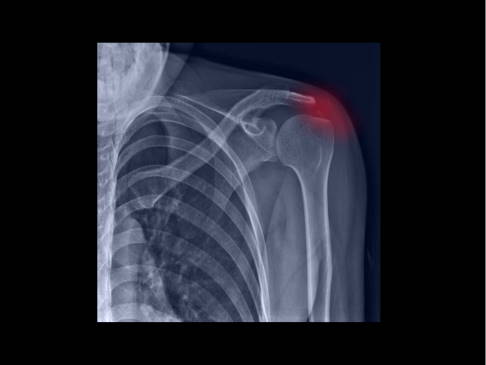

Eine Tendinitis ist eine Sehnenentzündung (lat. tendo "Sehne" und griech. -itis "entzündlich"). Häufige Ursachen für Tendinitiden sind eine Überlastung durch Sport bzw. Arbeit oder degenerative Veränderungen.

Bemerkbar macht sich eine Tendinitis durch Schmerzen bei Bewegung, d. h., wenn der Muskel kontrahiert wird, dessen Sehne betroffen ist. Die Behandlung erfolgt mit entzündungshemmenden Medikamenten (NSAR), vorübergehender Ruhigstellung und physikalischer Therapie, manchmal unterstützt durch entsprechende Physiotherapie. Führt dies nicht zu Erfolg, kann eine Operation in Erwägung gezogen werden.